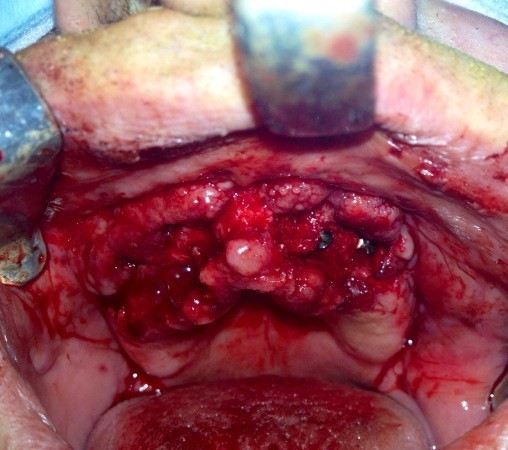

Implantologia avanzata con contestuale rimozione impianti e cisti

Video di una Parte dell'intervento in cui si puo' vedere la comunicazione tra impianti rimossi e pavimento nasale.